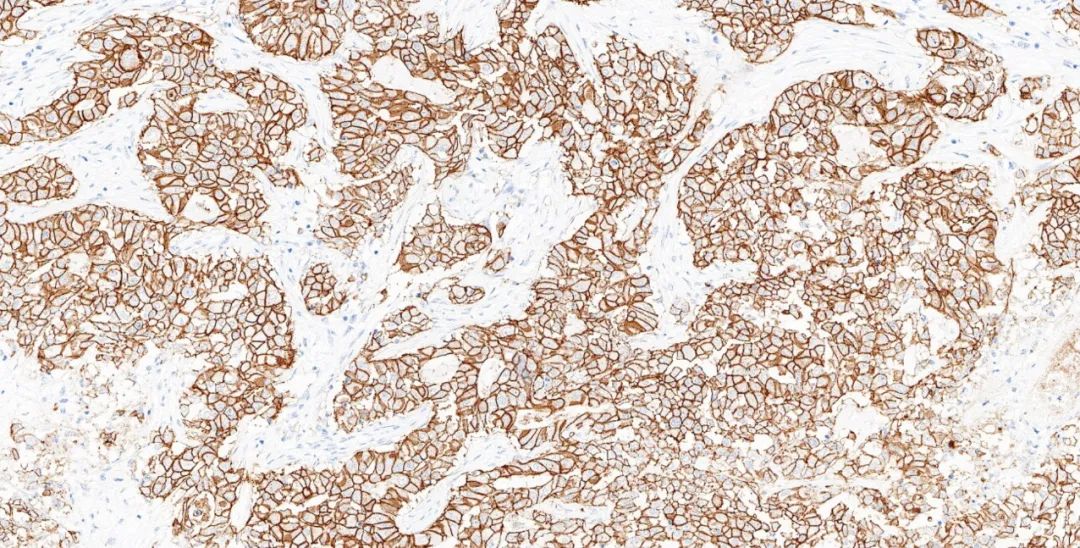

圖5.基因科技免疫組化測評結果圖:HER2(GT2245) 乳腺癌3+

384個實驗室參加了測試,獲得了82%(54%優異)的通過率,與最近的B32輪評估幾乎相同,與前三次評估B29-B31中的水平相比略有降低。結果不足的主要原因是假陰性結果或信噪比差,影響了讀數。